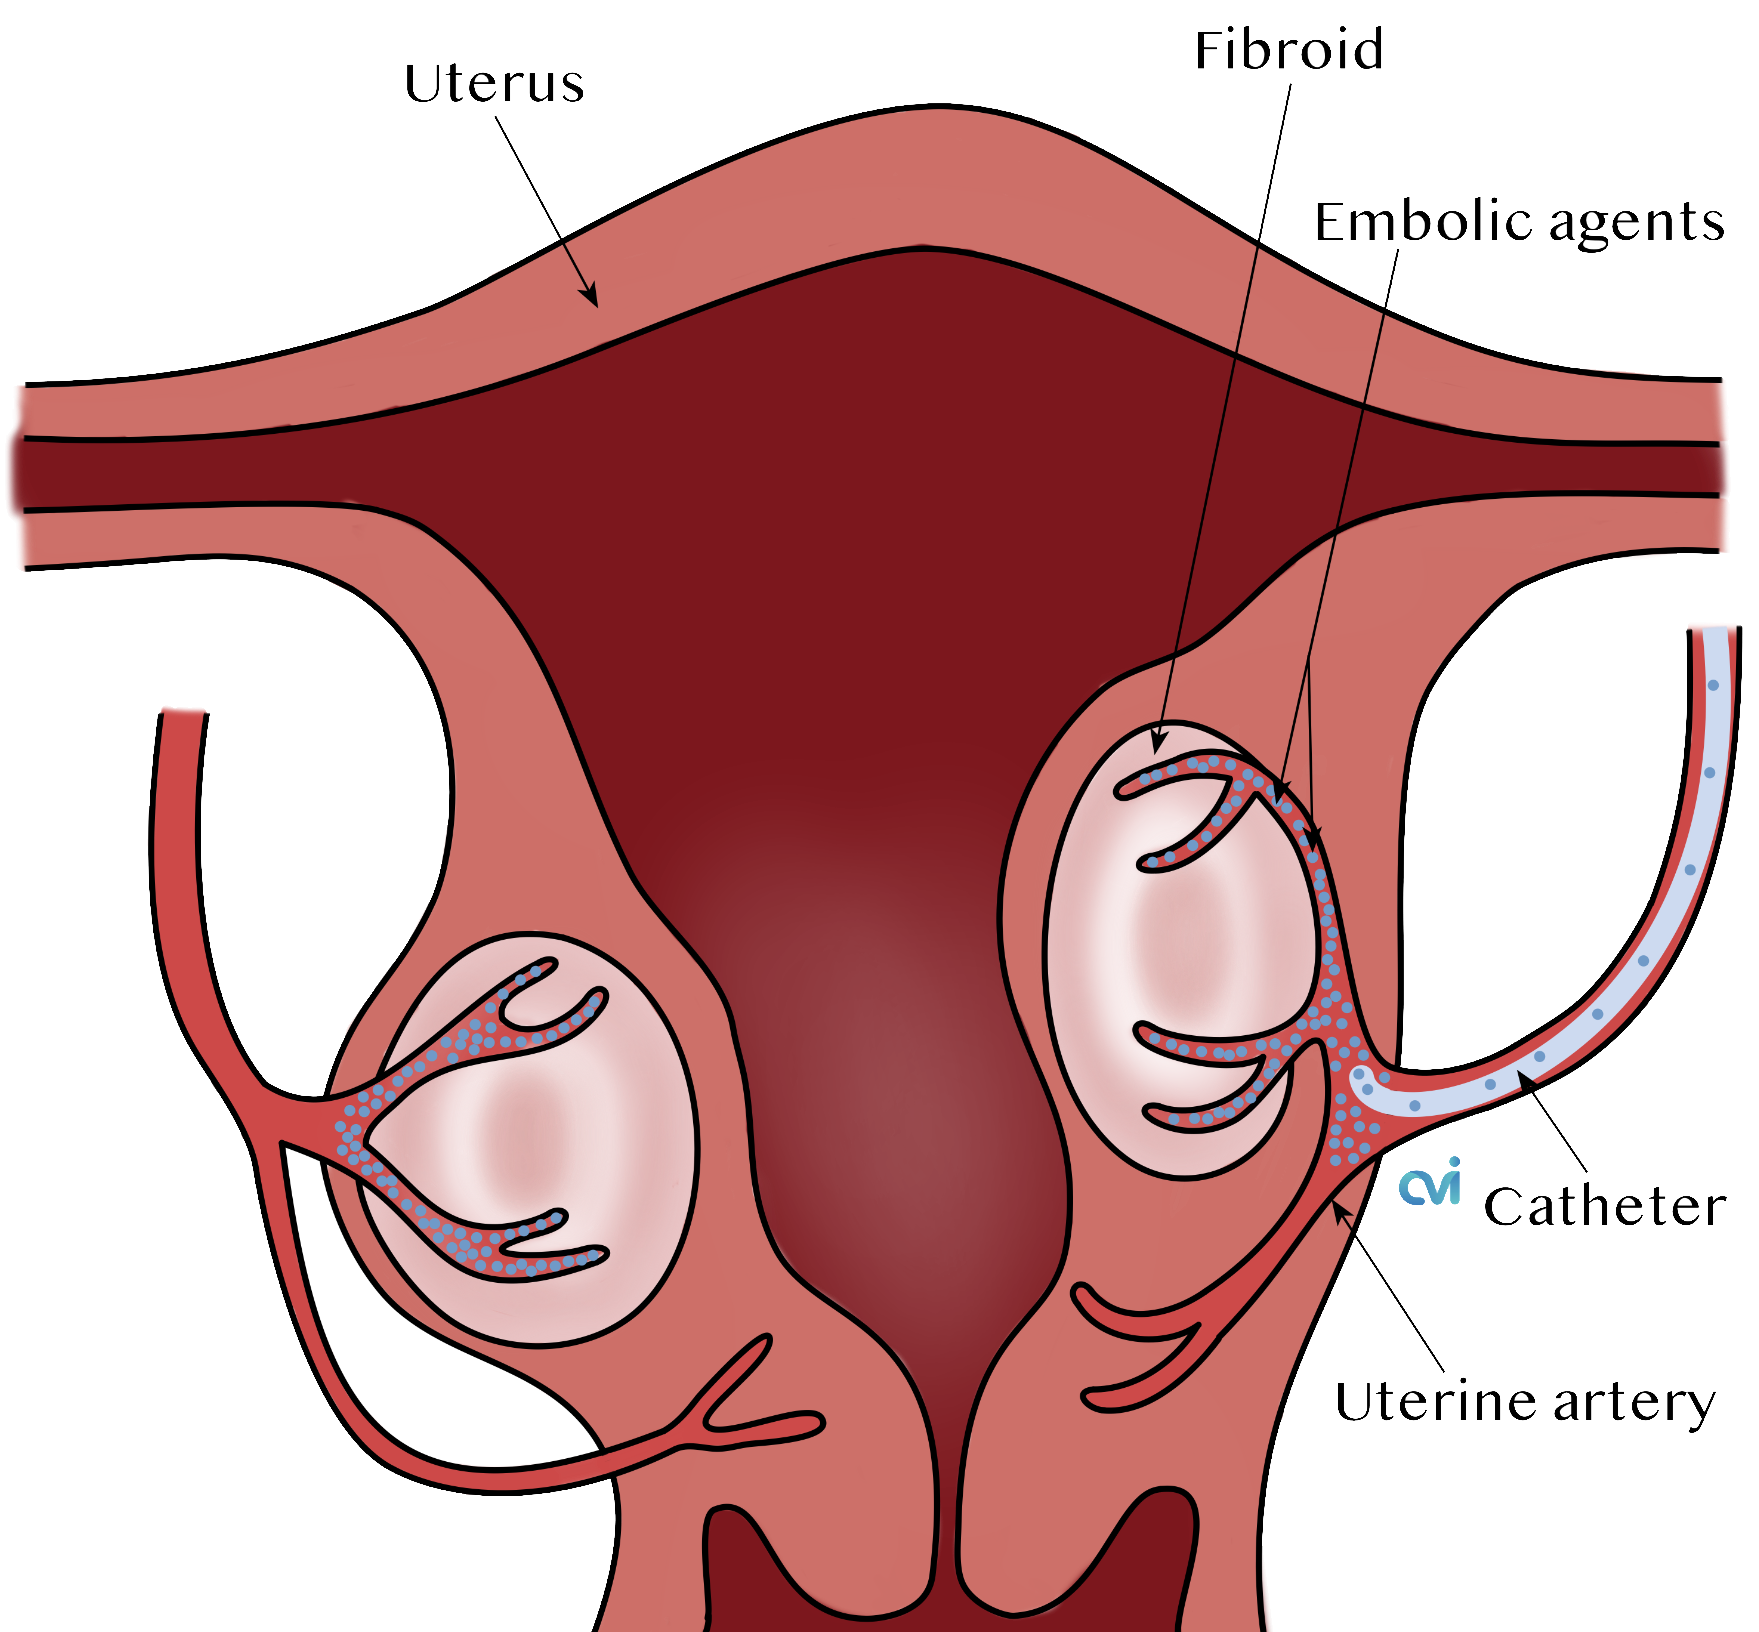

Deborah’s Uterine Fibroid Embolization | Fibroid Institute Dallas, TX

6 Uterine Fibroid Treatment Options – Vejthani Hospital

Épinglé sur Fibroid Embolization Procedure

About Uterine Fibroids | Fibroid Institute Texas

California’s Top Doctor for Uterine Fibroid Embolization – Los Angeles, CA